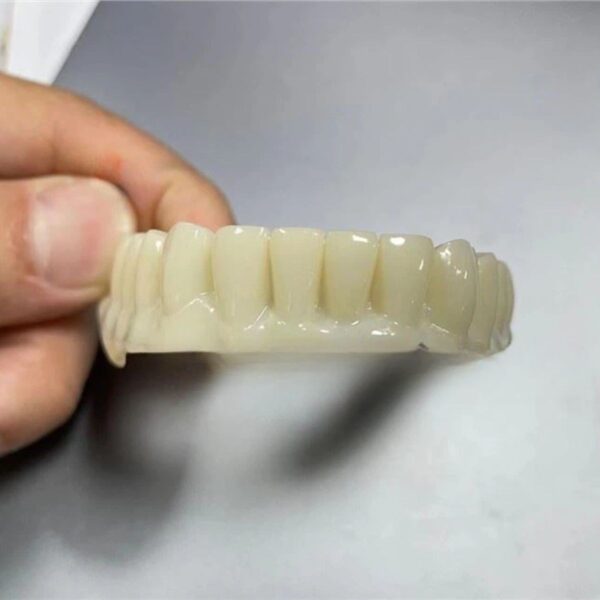

Conservative designs with perfect internal adaptation.

Stop grinding contacts. Receive designs that seat passively every time.